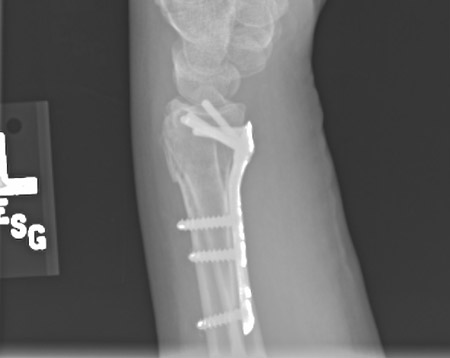

Plate fixation after open reduction with a volarly placed plate and screws

From the collection of Dr Chaitanya S. Mudgal